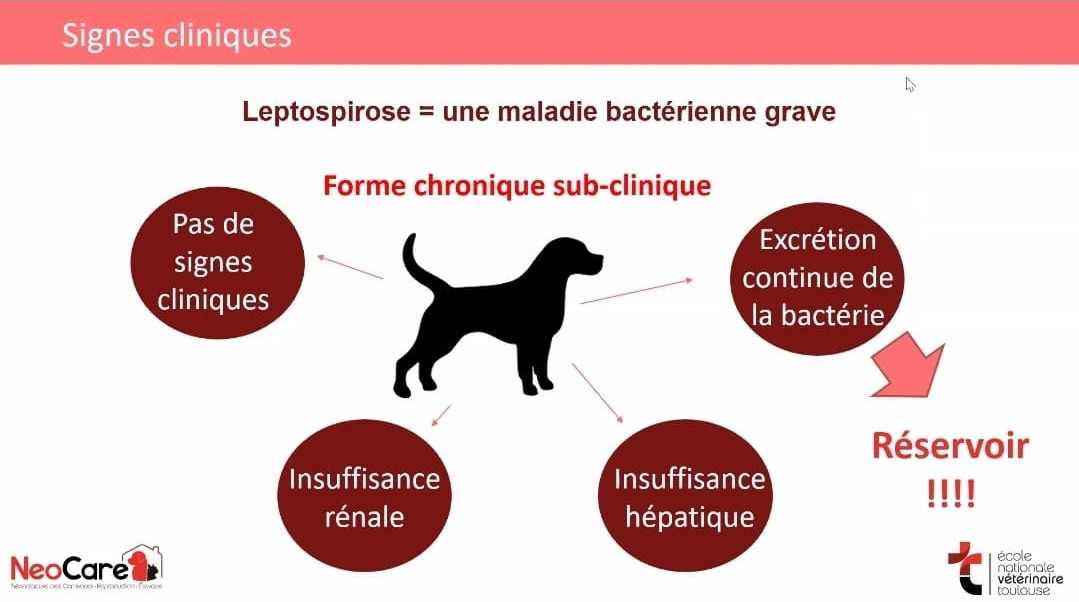

La Leptospirose Canine : Pourquoi la Vaccination est Essentielle

La Leptospirose Canine : Pourquoi la Vaccination est Essentielle

Les Symptômes de la Leptospirose

Les Symptômes de la Leptospirose La Maladie de Carré et l’Hépatite de Rubarth – Les Menaces Virales du Chiot

La Leptospirose Canine : Pourquoi la Vaccination est Essentielle

La Leptospirose Canine : Pourquoi la Vaccination est Essentielle

Les Symptômes de la Leptospirose

Les Symptômes de la Leptospirose La Maladie de Carré et l’Hépatite de Rubarth – Les Menaces Virales du Chiot